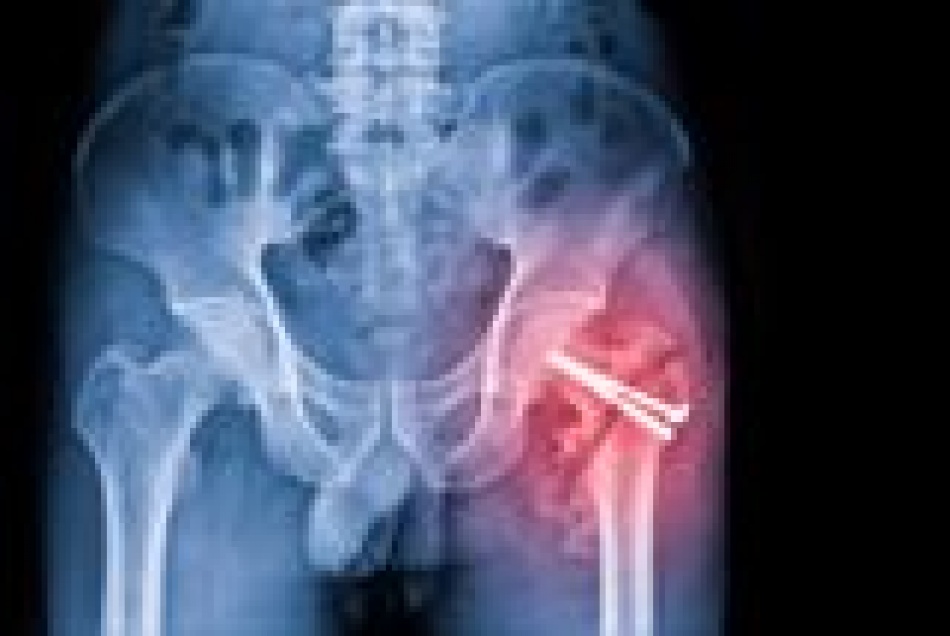

Почему переломы бедра у пожилых опаснее, чем кажется на первый взгляд

Скрытая угроза: как один перелом бедра меняет всю жизнь пожилых людей

С возрастом даже незначительная травма может обернуться серьезными последствиями. Особенно это касается переломов бедра у пожилых людей. На первый взгляд кажется, что речь идет о стандартной травме, но на деле ситуация куда сложнее. По оценке Петербург2.ру, число подобных случаев в мире неуклонно растет, и к 2050 году может превысить 4 миллиона ежегодно.

Причины переломов бедра у пожилых разнообразны. Наиболее частый фактор - остеопороз, который особенно часто встречается у женщин старшего возраста. Слабость мышц, проблемы с равновесием, хронические заболевания вроде диабета или анемии, а также снижение массы тела - все это увеличивает риск. Иногда перелом происходит даже без падения: достаточно неудачно встать с кровати или сделать шаг. В таких случаях речь идет о патологических переломах, когда кость уже ослаблена болезнью.

Главная опасность - не сам перелом, а то, что он сигнализирует о глубинных проблемах со здоровьем. Если у человека уже есть остеопороз или он страдает от недостатка питания, перелом бедра становится тревожным звоночком. Это не просто травма, а признак системных нарушений в организме.